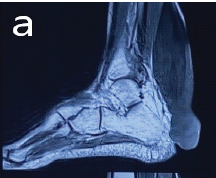

Calcaneus and Traumatic Stress Fracture

Elizabeth Jelpke , Saphalya Pattnaik , Gur Aziz Sidhu

………………………………p.185-187